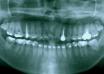

case dot 改善後牙錯咬

case dot 改善前牙錯咬

case dot 排整牙齒

case dot 扶正大臼齒

case dot 拔牙改善嚴重擁擠及中...

case dot 改善齒間縫隙過多